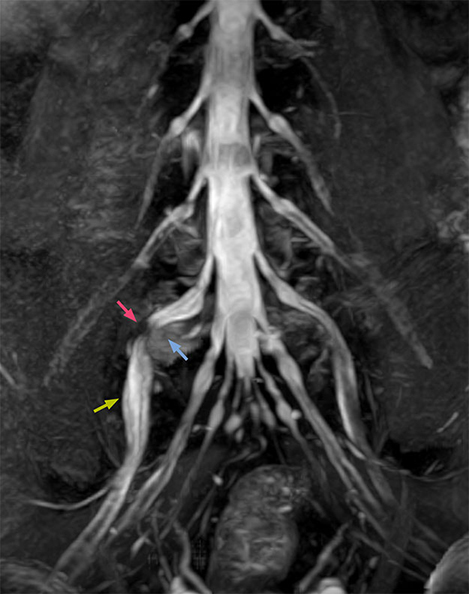

According to Tanji, methods such as ProSet FFE, STIR or 3D VISTA are anatomically nonselective because background signals, for instance from blood vessels, often interfere with nerves, which hampers evaluation of details, especially at the peripheral side of the nerves.

“The intra-luminal signal of veins, especially around the intervertebral space, can be suppressed well with NerveVIEW. As a result, we can easily observe the detailed nerve structure around the posterior ganglion,” he says. “This is why we use 3D NerveVIEW for intraforaminal stenosis and extraforaminal stenosis/herniation (lateral disc herniation). On the other hand, if herniation is suspected to exist inside the dorsal root ganglion (DRG), balanced TFE or ProSet-FFE is applied. NerveVIEW is not suitable for evaluating the median type of herniation.”

Because the obtained NerveVIEW images often exhibit a high signal in the intervertebral discs, we use partial MIP images to eliminate such intervertebral disc high signals. MIP image generation is based on the  center of the coronal stack, and RAO (right anterior oblique) and LAO (left anterior oblique) images rotated in the range of 45 degrees are used for diagnosis.

“NerveVIEW can clearly show nerve courses and presence of nerve compression. However, when multiple abnormalities are seen, it can still be hard to determine which nerve is causing the symptoms,” says Dr. Yabuki. “In our experience so far, we see abnormal findings on NerveVIEW in about 70% of elderly patients. As the pain is usually caused by only one nerve, we thus need to find the exact corresponding nerve.”

“With a nerve root block, the patient's pain is improved by infiltration of local anesthesia directly around the nerve root considered to be responsible. Knowing such nerve root block findings prior to image interpretation, helps to easily recognize abnormal findings on NerveVIEW as well. In other words, without a priori knowledge, based on symptoms and/or nerve root block findings, we must be aware of the possibility of overdiagnosis.”